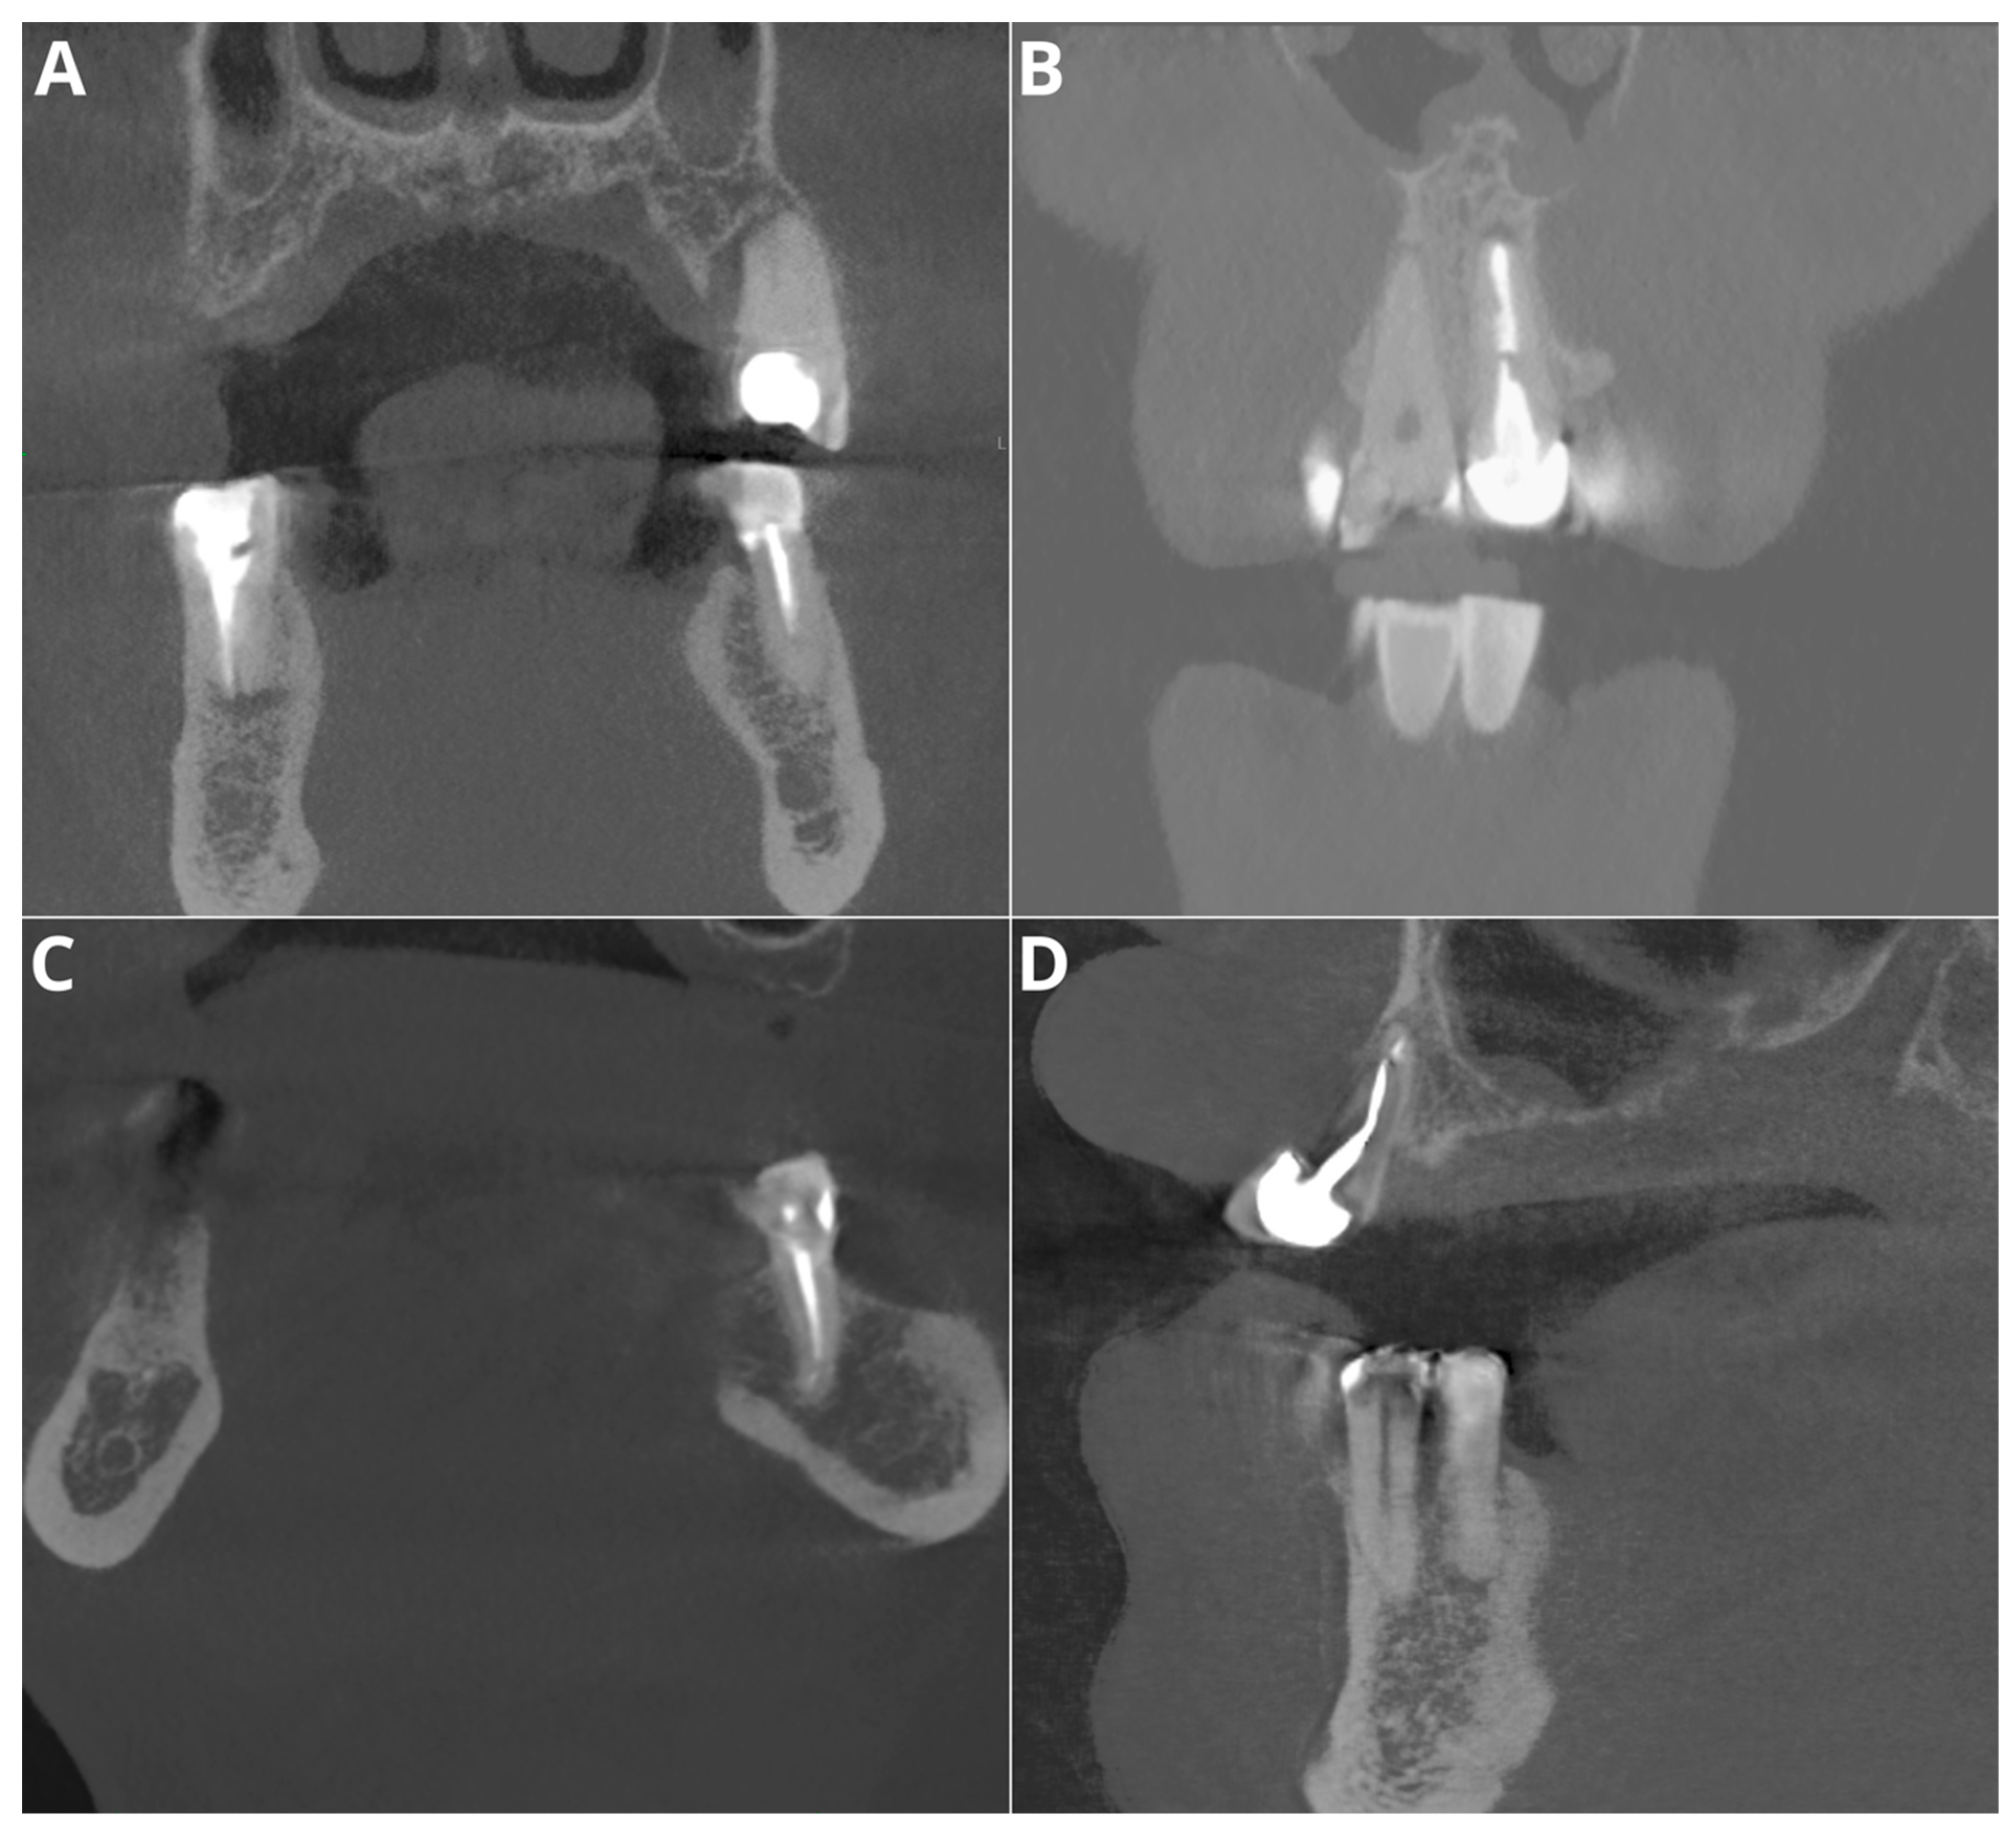

- Voids in filling

- Short filling

- Voids in filling—identification of radiolucent areas within the filling that indicate the presence of voids.

- Short filling—assessment of the extent of the filling material if it falls short of the tooth apex.